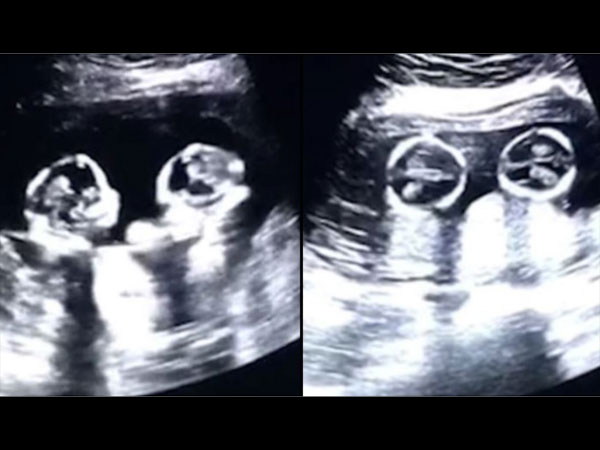

अल्ट्रासाउंड में दिखी गर्भ में जुड़वां बच्चों की लड़ाई, वीडियो हुआ वायरल

गर्भ में जुड़वां बच्चों की खबर सुन कर किसी भी मां बाप को बहुत खुशी होगी लेकिन तब आप कैसी प्रतिक्रिया देंगे जब आपको मालूम चले कि इस दुनिया में कदम रखने से पहले ही उन बच्चों ने गर्भ में ही लड़ना शुरू कर दिया है? सुनने में ये काफी अजीब लगेगा। यहां हम एक वीडियो शेयर कर रहे हैं जिसमें जुड़वां शिशु स्कैन के दौरान एक दूसरे से दो दो हाथ करते दिखे। इस लेख के माध्यम से आप भी देखें वो वीडियो।

सूत्रों के मुताबिक ये वीडियो पिछले साल का है जिसे चीन के एक व्यक्ति ने अपनी प्रेगनेंट पत्नी के अल्ट्रासाउंड के दौरान रिकॉर्ड किया। महिला के गर्भ में जुड़वां बच्चियां थी और अल्ट्रासाउंड के वक्त वो चार महीने पूरे कर चुकी थीं।

अल्ट्रासाउंड स्कैन में नजर आया कुछ अलग

अल्ट्रासाउंड स्कैन वीडियो में दोनों भ्रूण एक दूसरे को लात और हाथ से मारते हुए नजर आए। पिता ने सोशल मीडिया पर इस वीडियो को शेयर किया और देखते ही देखते ये वायरल हो गया।

गर्भ में पल रही बच्चियों के पिता थे बहुत खुश

उस व्यक्ति ने बताया कि वो अपनी बच्चियों जिन्होंने इस दुनिया में अभी कदम भी नहीं रखा उन्हें एक दूसरे से लड़ते देख कर बहुत खुश हुए।

सोशल मीडिया में वायरल हिट हुआ ये वीडियो

ये वीडियो भले ही अब तकरीबन एक साल पुराना हो चुका है और इन बच्चियों का जन्म भी हो गया है। लेकिन इसके बावजूद ये वीडियो सोशल मीडिया पर एक बड़ा हिट साबित हुआ। आंकड़ों के मुताबिक इस वीडियो को 2.5 मिलियन बार देखा जा चुका है और इस पर 80,000 से ज्यादा कमेंट्स आए हैं।